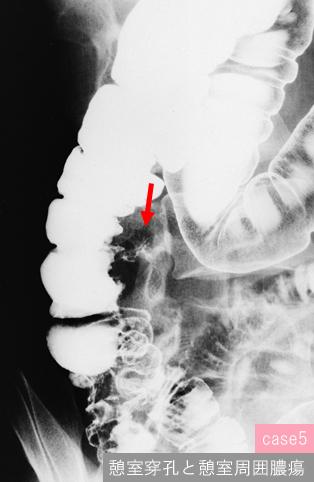

질환(병리주체)의 분류 기타/

부위(장기별) 대장/상행

검사방법 X-P